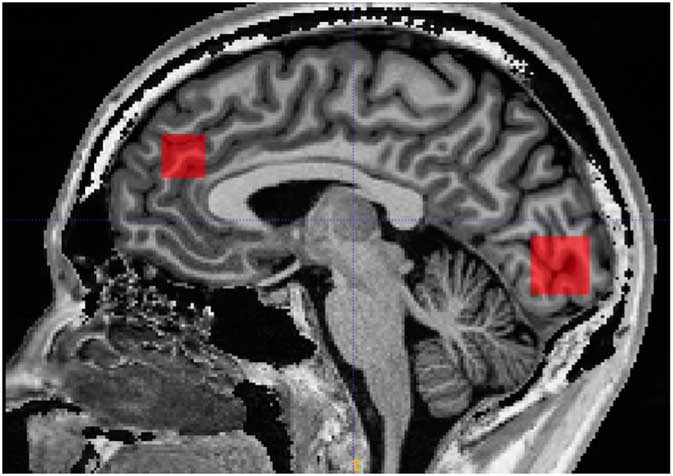

Scanning was performed on a 3 Tesla MR system (Siemens, Trio, Erlangen, Germany) with a body coil transmitter and a 32-channel receive head array. Data were acquired from a 30×15×15 mm voxel located in PFC and a 25×20×20 mm voxel located in OCC. A structural T1-weighted MPRAGE image (TR/TE 2420/4.58 ms, 1 mm isotropic resolution, scan time 10 min and 55 s) was acquired and used for manual positioning of the voxels and subsequent tissue segmentation. The PFC voxel was positioned just superior to genu of corpus callosum with the long axis along the right/left direction. The occipital voxel was oriented parallel to the occipital bone and just above the tentorium (Fig. 1).

Fig. 1 Illustration of prefrontal and occipital voxel placement.